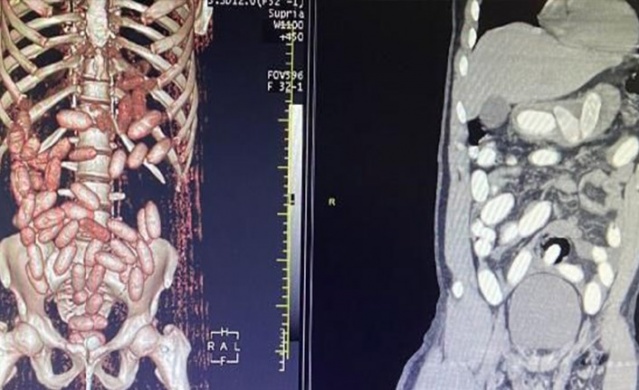

Gümrük Muhafaza ekiplerince savcılık talimatı doğrultusunda detaylı bilgisayar tomografi çekilmesi için sağlık kuruluşuna götürülen 6 yolcunun yapılan tarama ve muayenelerinde 761 adet ve toplam ağırlığı 10 kilo 420 gram kokain tespit edildi.